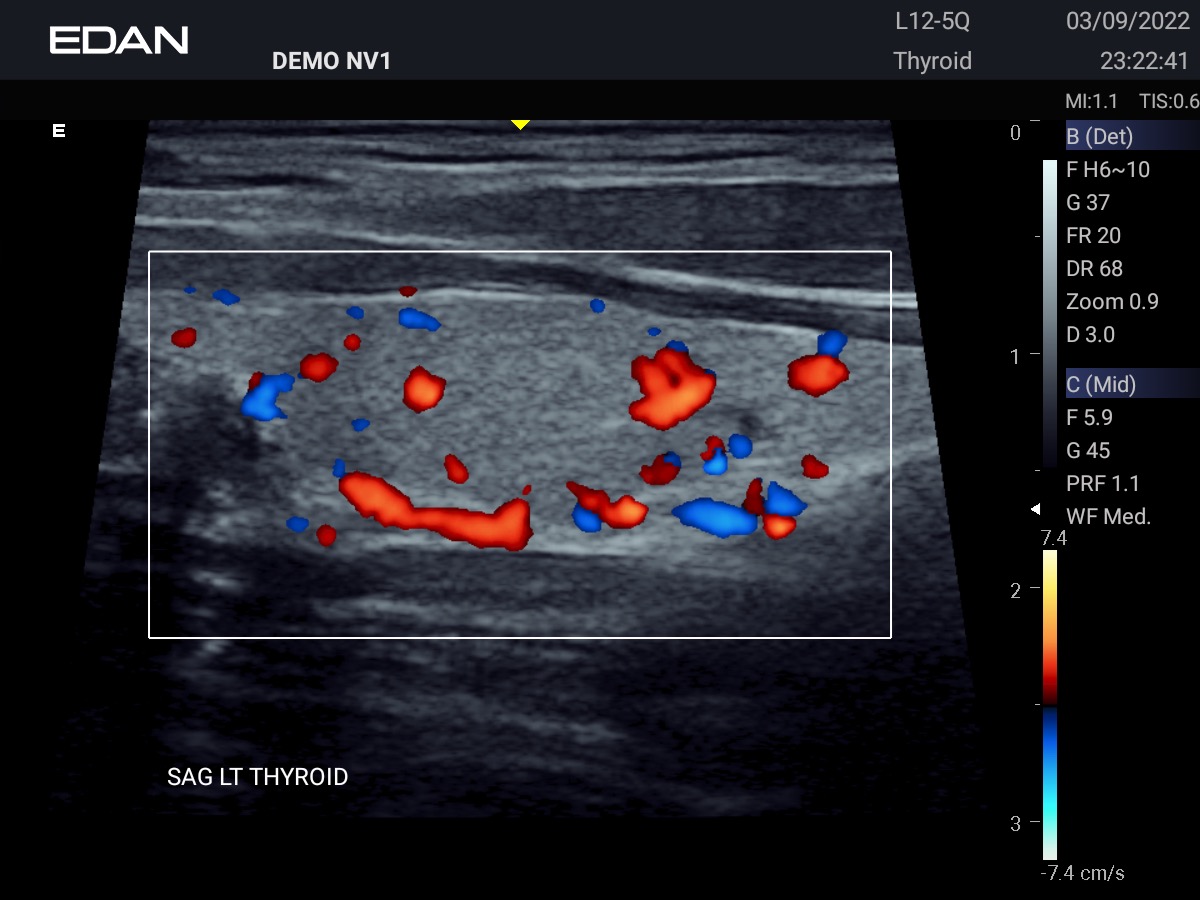

Clareza impressionante

Construído com a inovadora tecnologia Edan TAI e várias tecnologias de processamento de imagem, o Acclarix AX3 pode exibir perfeitamente a imagem de ultrassom em diferentes modos, auxiliando o ultrassonografista a fazer diagnósticos mais precisos.

Galeria de Imagens